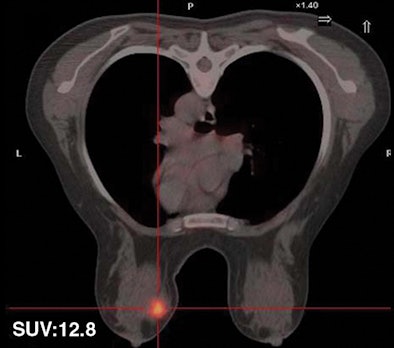

| Thirty-two-year-old woman with ductal infiltrating adenocarcinoma measuring 18 mm in maximum transverse diameter. Axial fused PET/CT images obtained with patient in prone position at time point 1 (above) and time point 2 (below) show corresponding standard uptake values. |